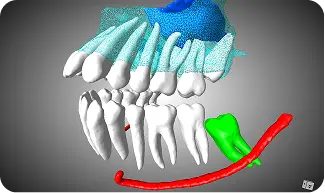

Board-certified reports for implants, TMJ, and airway with systematic incidental finding screenings.

High-precision DICOM conversion into 3D anatomical models and STL files ready for surgical guides.

"I send every complex endo case to CBCTreads before initiating treatment. Dr. Abdelkarim’s interpretations help me localize canals, evaluate periapical pathology, and detect fractures that aren’t always visible in-office. His insights often change my treatment strategy—and improve outcomes. The clarity and diagnostic accuracy are unmatched."